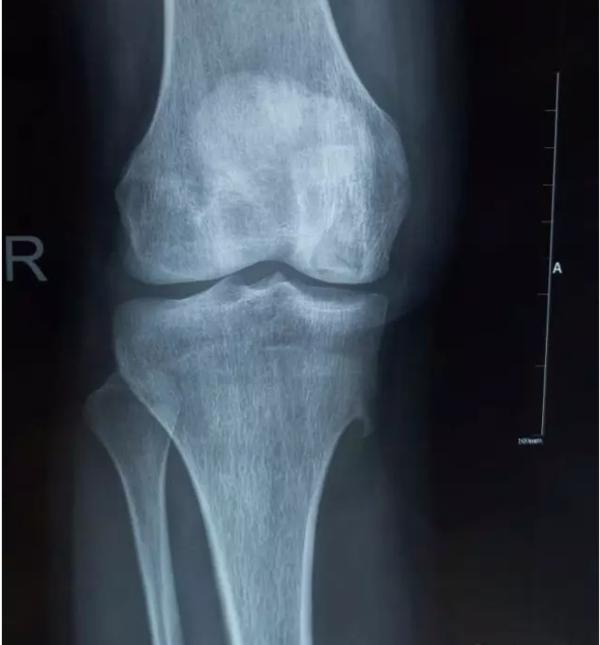

膝关节不均匀沉降术后患者X线片(下图)

中期:骨关节炎表现为膝关节持续性疼痛,活动后或上下楼梯时加重,压痛明显; X线片上可见增生的骨赘,关节间隙出现狭窄,多为不对称性狭窄。

晚期:骨关节炎表现为膝关节明显疼痛,休息后常无缓解,伴有活动受限,可并发畸形,X 线片可见关节周围有明显的骨赘形成,或可见游离体,关节间隙明显狭窄,甚至消失。